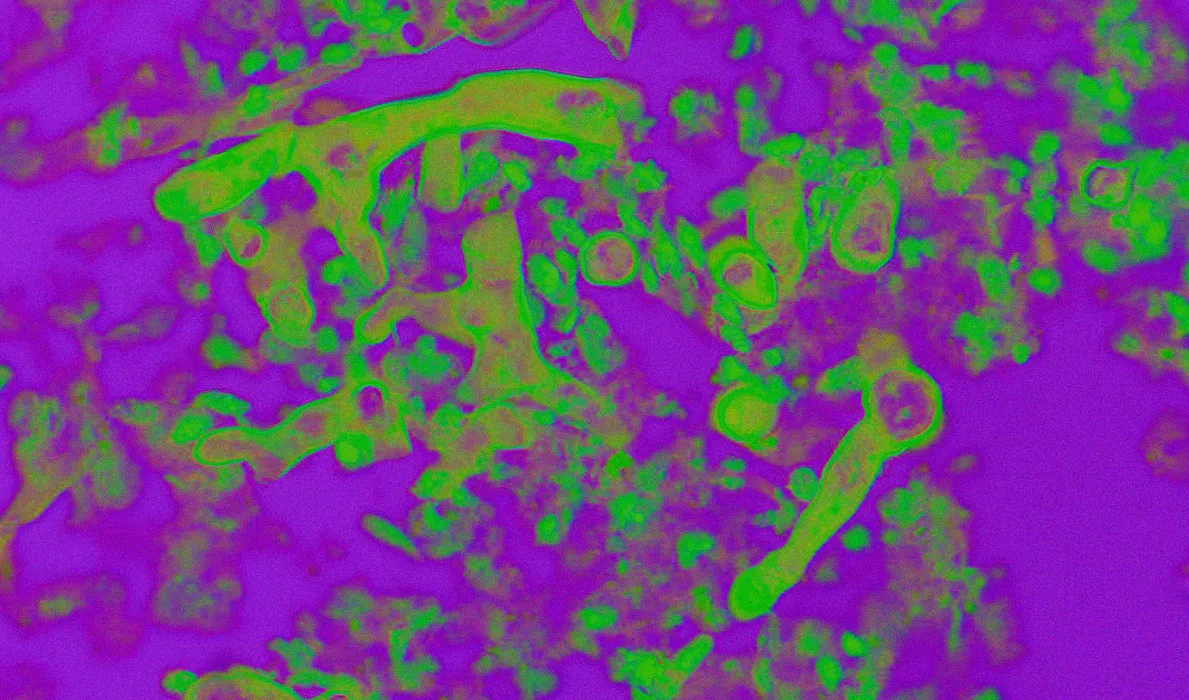

La mucormycose est un type d’infection fongique qui attaque des zones sensibles comme le cerveau, les poumons et les sinus. Bien qu’elle soit courante dans la nature, un système immunitaire sain peut généralement y résister. Cependant, lorsque le champignon s’installe, il peut être fatale pour près de la moitié des personnes infectées.

Le champignon responsable est présent dans l’environnement, notamment dans le sol et les matières organiques en décomposition. L’infection peut survenir par inhalation de spores ou par contact avec des plaies.